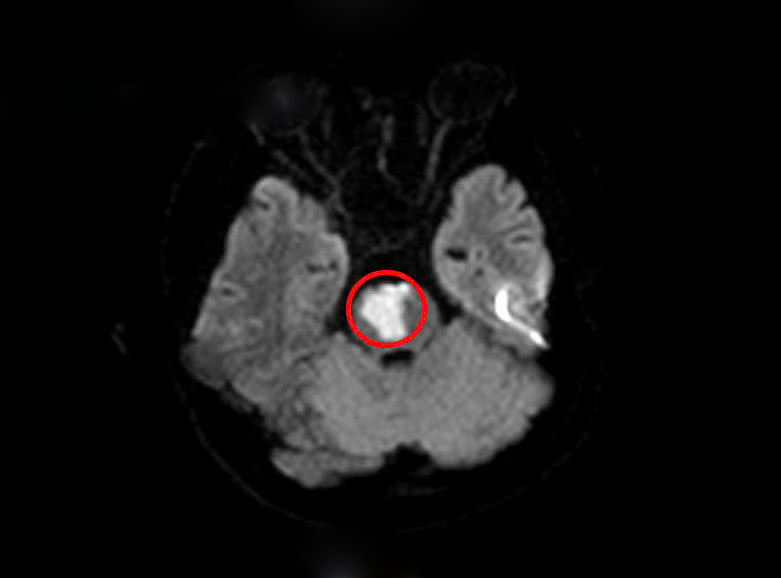

Sau khi khai thác tiền sử, các bác sĩ nghĩ nhiều đến tình trạng đột quỵ não và cho chỉ định tiến hành chụp MRI sọ não. Kết quả cho thấy người bệnh có khối nhồi máu tiểu não, cầu não do tắc động mạch thân nền.

Tổn thương nhồi máu vùng tiểu não của người bệnh(Vùng khoanh tròn màu đỏ)